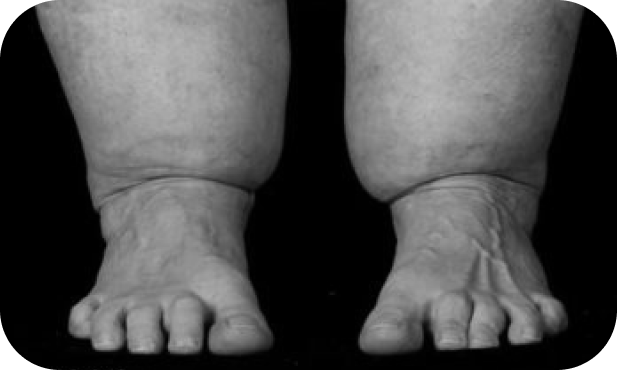

El lipedema no es solo una cuestión estética. Es una condición médica progresiva que causa acumulación anormal de grasa en piernas y brazos, dolor crónico, pesadez extrema y, en muchos casos, vergüenza e incomprensión. Muchas mujeres pasan años sin diagnóstico, sintiéndose frustradas y sin respuestas.